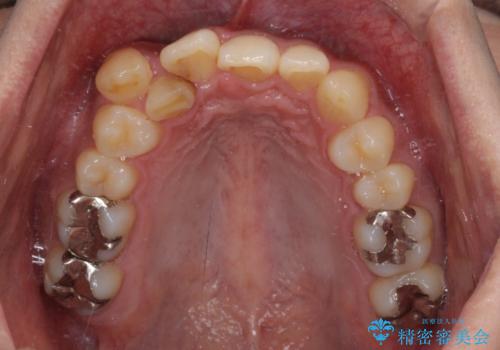

- 上顎の八重歯と正中のズレを気にして来院された患者様です。

八重歯による叢生は著しく、それにより上顎の正中が大きく右にずれている状態でした。

口元の突出感は感じていなかったことと、奥歯の咬み合わせを考慮し、上顎のみ左右の第一小臼歯を抜歯してワイヤー装置にて矯正治療を行うこととしました。